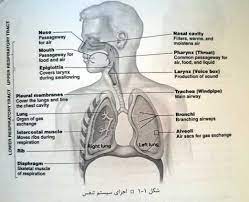

قیمت: 136٬000 تومان - دسته بندی فایل: پاورپوینتفیزیولوژی دستگاه تنفس

فروش ویژه پاورپوینت حرفه ای فیزیولوژی دستگاه تنفس با تخفیف استثنایی فقط 99 هزار تومان تعداد اسلاید: 125